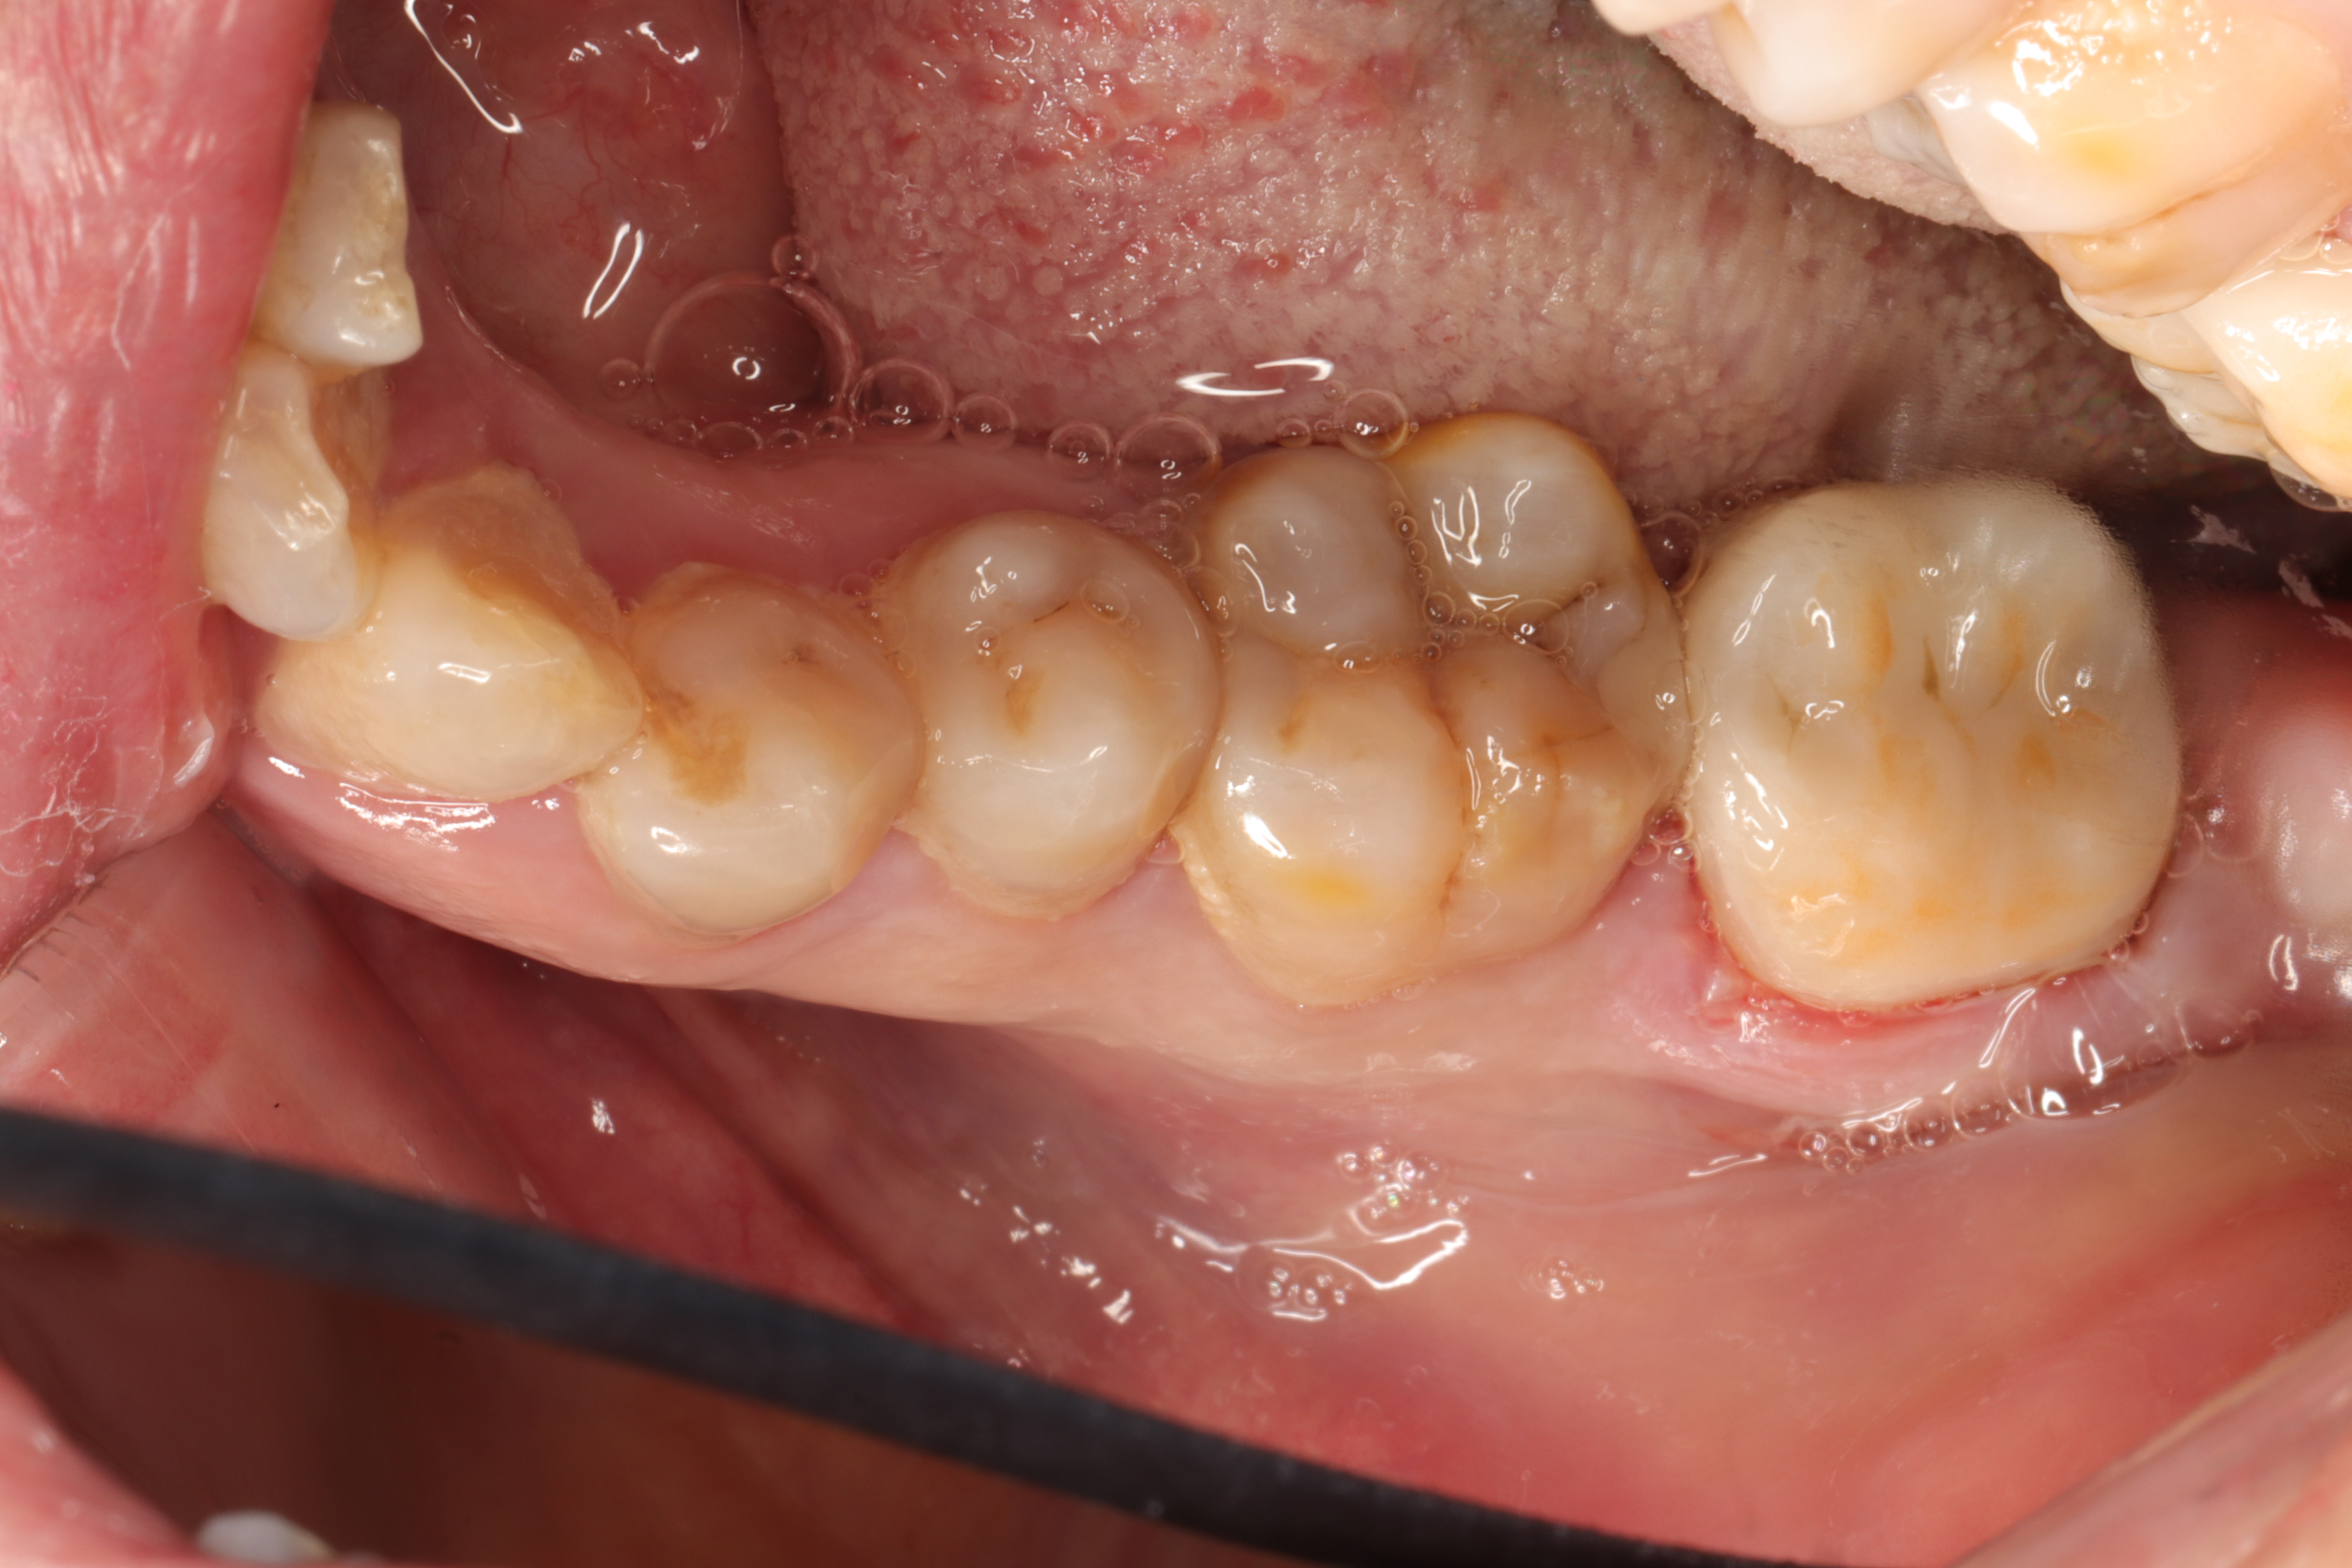

即刻粘接术后照

术前术后对比